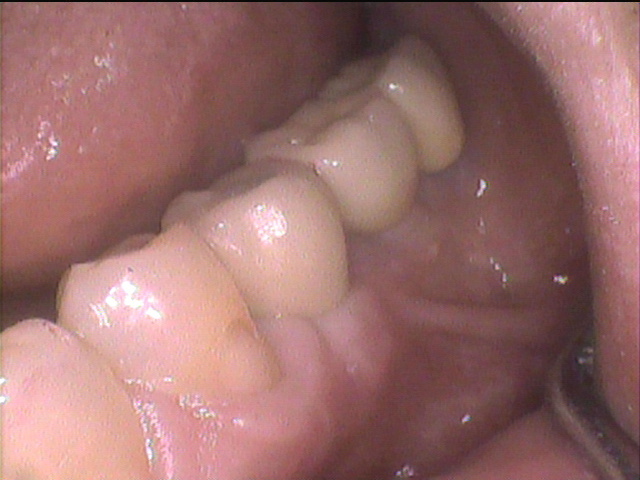

治療後写真

- 術後の口腔内写真です。

自分の歯と同じ様な外観に修復できました。

【院長所見】ソケットプリザベーションという方法を用いることで骨の吸収を抑え、インプラントを行う場合でも、審美的にも機能的にも自分の歯と同じように咬むことが出来るように骨の造成が出来ています。